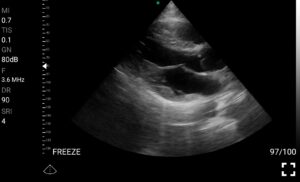

Παραδείγματα

Ολες οι παραπάνω απεικονιστικές εξετάσεις έχουν ληφθεί από φορητή συσκευή όπως: Apple Iphone, Tablet, Samsung Mobile Phones και διάφορες άλλες φορητές συσκευές.

• Doppler καρδιακών βαλβίδων: Βασική εκτίμηση στένωσης/ανεπάρκειας.

• Καρδιακές βαλβίδες: Ανίχνευση παθολογιών όπως στένωση, ανεπάρκεια, βαλβιδικές βλάβες.